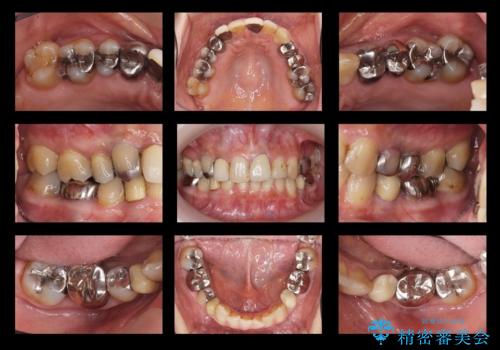

50代女性 銀歯をとって白いつめものに 全体的な治療

- 50代女性

- 銀歯や被せ物のやり替えをご希望で来院。悪いところはすべて治していきたいとのことでした。

根の治療を含めてしっかりやり直しを行いました。

本数も多く、時間はかかりましたが、しっかり通いきっていただきました。